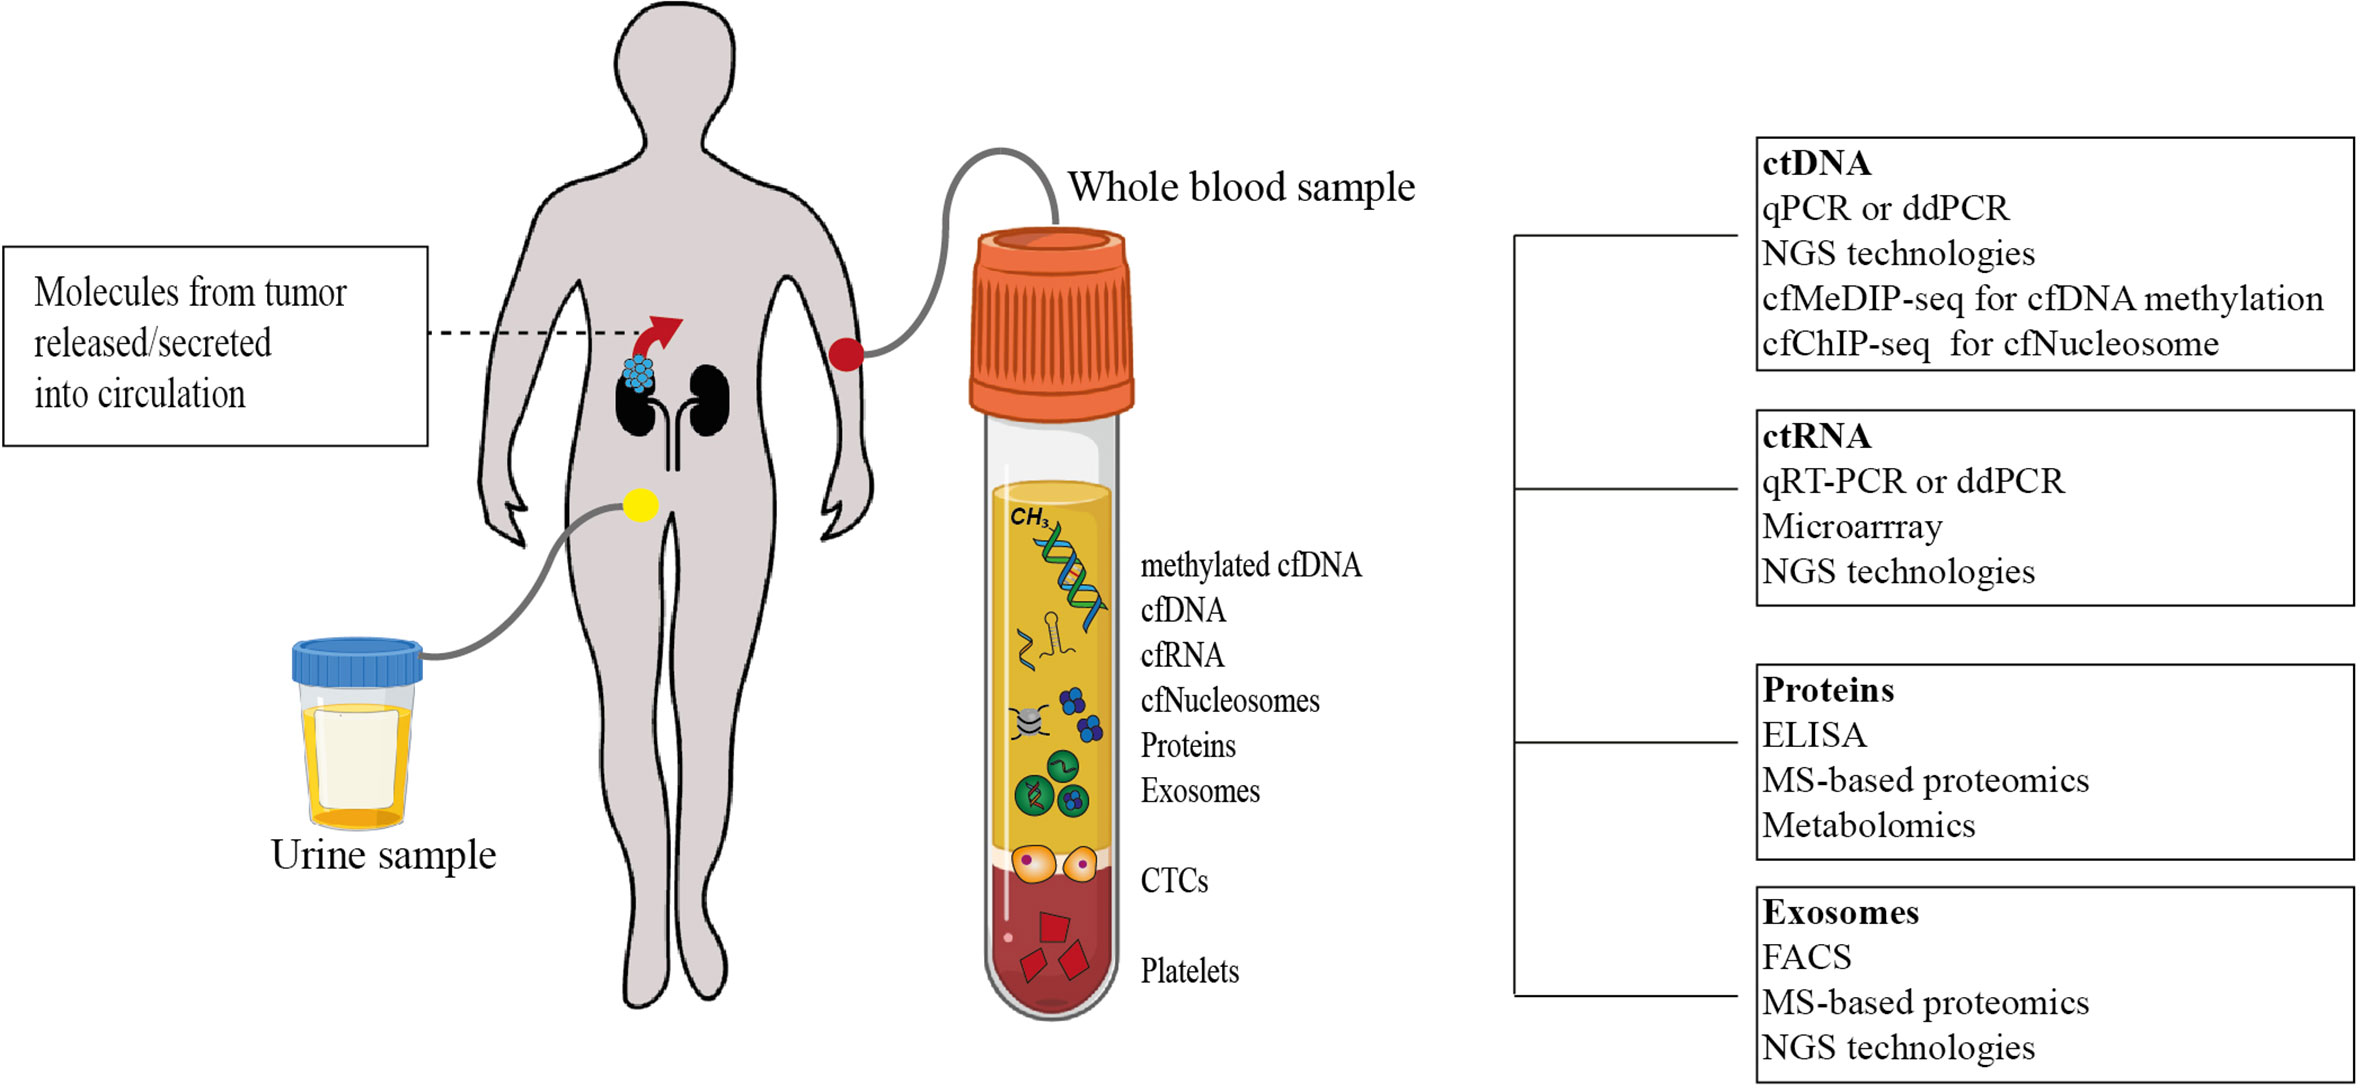

Frontiers | Liquid Biopsies In Renal Cell Carcinoma—Recent Advances And

www.frontiersin.org renal frontiersin biopsies metastatic carcinoma advances promising fonc

Liquid Biopsy

biopsy liquid cancer lung biomarkers applications future gene application current cell diagnostics role separation techniques various isolation

Biopsy liquid cancer lung biomarkers applications future gene application current cell diagnostics role separation techniques various isolation. Adenocarcinoma mucinous biopsy tnm bilateral manifesting. Ameloblastoma malignant metastatic tumor misdiagnosis